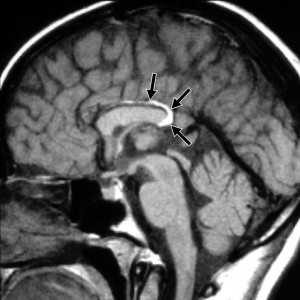

Кисты средней линии - киста прозрачной перегородки (cavum septi pellucidi), полость Верге (cavum Vergae) и киста промежуточного паруса (cavum veli interpositi) - являются нормальными структурами головного мозга плода. В течение 6 месяцев после рождения у большинства людей они запустевают, но могут и сохраниться, визуализируясь при этом на МРТ головного мозга. По-видимому, эти полости не имеют клинического значения и относятся к случайным находкам при томографии. Киста прозрачной перегородки (еще называют V желудочком) является медиальной стенкой боковых желудочков и ограничена спереди коленом мозолистого тела, сверху мозолистым телом и сзади столбами свода . Полость Верге представляет собой продолжение кисты прозрачной перегородки кзади и расположена между телами желудочков . Обычно обе кисты сочетаются. Киста промежуточного паруса расположена в крыше III желудочка (tela choroidea), между треугольниками боковых желудочков на уровне отверстий Монро. Она ограничена сверху мозолистым телом, cзади цистерной четверохолмия и снизу III желудочком.

Кисты средней линии - киста прозрачной перегородки (cavum septi pellucidi), полость Верге (cavum Vergae) и киста промежуточного паруса (cavum veli interpositi) - являются нормальными структурами головного мозга плода. В течение 6 месяцев после рождения у большинства людей они запустевают, но могут и сохраниться. По-видимому, эти полости не имеют клинического значения и относятся к случайным находкам при МРТ головного мозга . Киста прозрачной перегородки (еще называют V желудочком) является медиальной стенкой боковых желудочков и ограничена спереди коленом мозолистого тела, сверху мозолистым телом и сзади столбами свода. Полость Верге представляет собой продолжение кисты прозрачной перегородки кзади и расположена между телами желудочков (рис.105). Обычно обе кисты сочетаются. Киста промежуточного паруса расположена в крыше III желудочка (tela choroidea), между треугольниками боковых желудочков на уровне отверстий Монро. Она ограничена сверху мозолистым телом, cзади цистерной четверохолмия и снизу III желудочком.